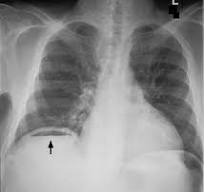

Image of Gas under diaphragm, best treatment?

a) IV fluids

b) Exploratory laparotomy

c) Laparoscopy

d) Paracentesis